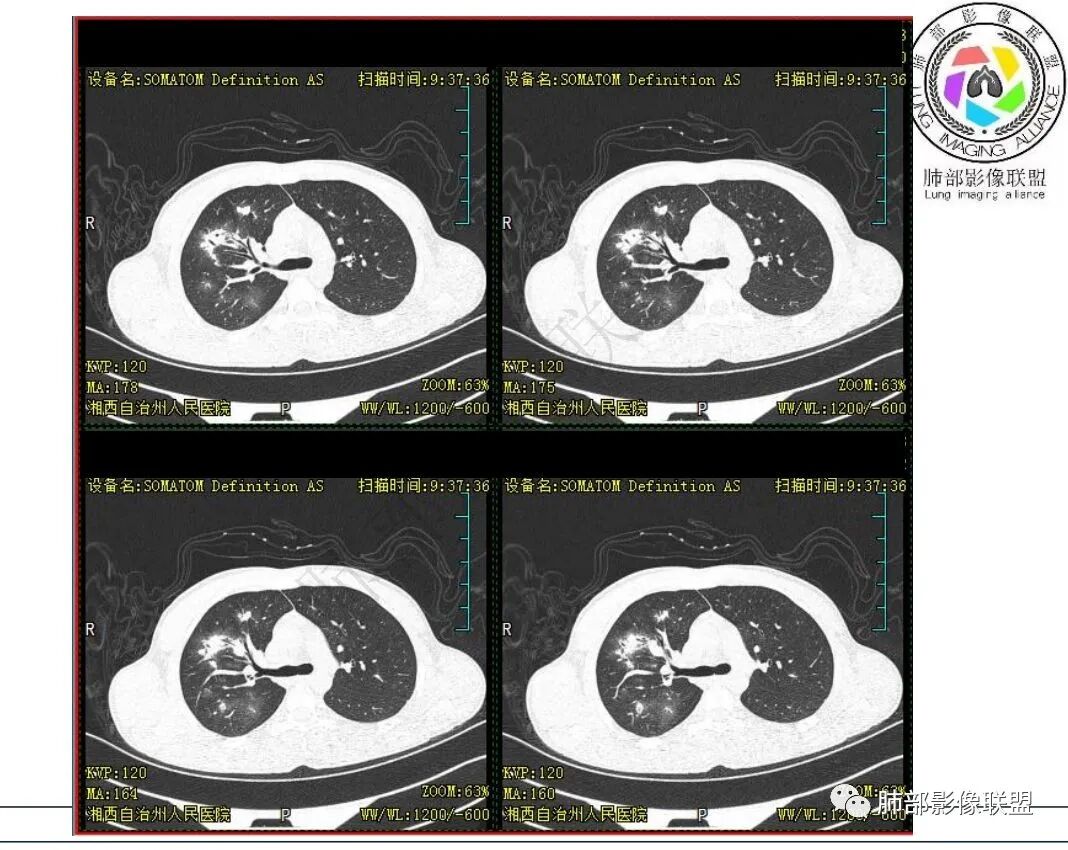

影像:右肺上叶多发实变影结节影,边界模糊,边缘收缩,伴多发空洞,洞壁光滑,部分支气管壁增厚。

3.首次CT提示:右肺上叶多发结节影及实变影,簇状分布,周围散在磨玻璃影,结节内多类圆形空洞,内壁光整,有一定张力,偶见液平。部分支气管壁增厚。

5.抛开分布不谈 其他的,临床中毒症状不明显、非易感人群,肺结节、实变、晕征、空洞等等都可以符合隐球感染。

本例病灶分布特点比较偏中央分布,不是我们常见的隐球外围胸膜下。看来诊断隐球,分布不能太绝对,至少不能作为绝对排除项。